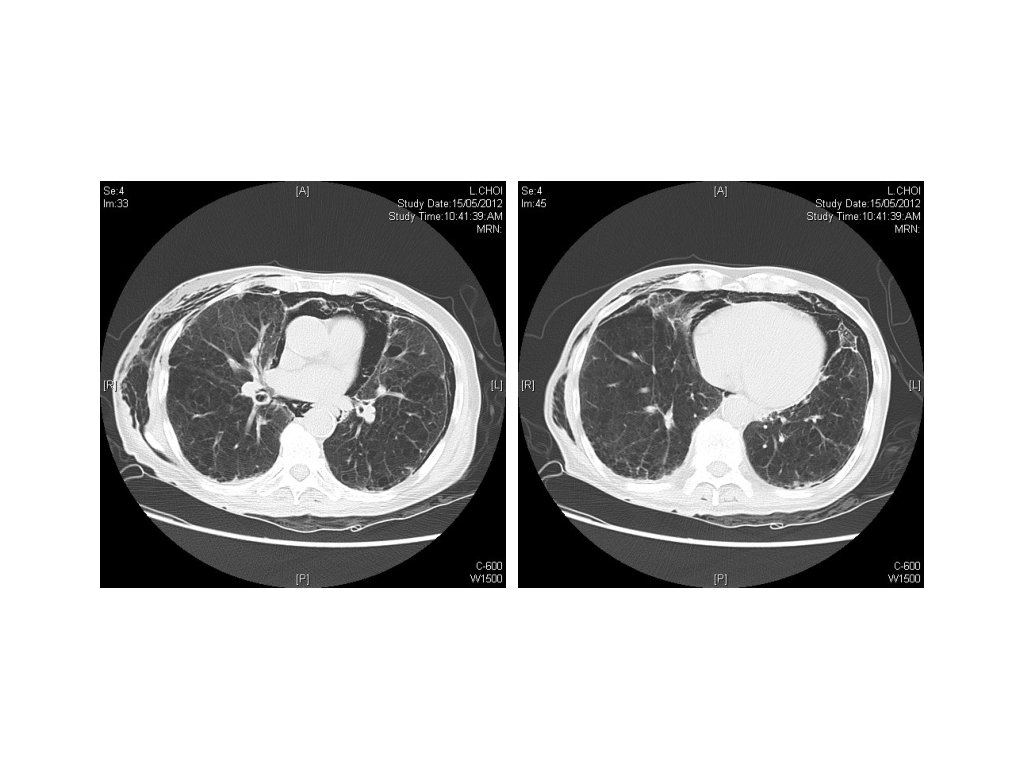

Case 3 • 90/M • Known COAD • Chest pain for a day

1. Besides the emphysematous and fibrotic changes of the lung, what are the X-ray findings? • Pneumomediastinum, pneumothorax, and subcutaneous emphysema 2. What are the two differential diagnoses? 3. What further imaging is helpful? 4. If the patient deteriorates with SOB, what will be your management?

1. Besides the emphysematous and fibrotic changes of the lung, what are the X-ray findings? • Pneumomediastinum, pneumothorax, and subcutaneous emphysema 2. What are the two differential diagnoses? • Spontaneous pneumomediastinum and pneumothorax • Ruptured oesophagus 3. What further imaging is helpful? 4. If the patient deteriorates with SOB, what will be your management?

1. Besides the emphysematous and fibrotic changes of the lung, what are the X-ray findings? • 2. Pneumomediastinum, pneumothorax, and subcutaneous emphysema What are the two differential diagnoses? • Spontaneous Pneumomediastinum and pneumothorax • Ruptured oesophagus 3. What further imaging is helpful? • 4. Water soluble contrast study If the patient deteriorates with SOB, what will be your management? • Chest drain insertion